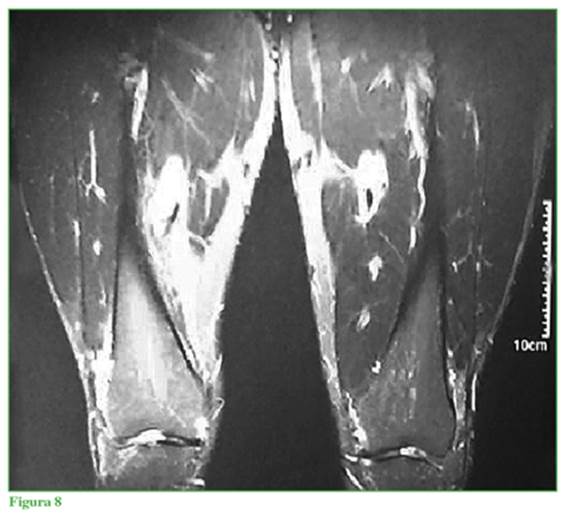

El estudio gold standard es la resonancia magnética nuclear, la que informó ausencia completa del vasto medial oblicuo (VMO) y diagnóstico presuntivo de agenesia completa de ese músculo en cortes axiales, sagitales y coronales en T1 y T2 (Figuras 4 a 8). Cortes coronales a diferentes alturas comparativas de ambos muslos en la región del tercio medio distal (Figuras 5 a 8).

Falta la representación habitual del músculo vasto medial derecho en toda su extensión, sugestivo de hipotrofia grave/agenesia muscular; vasto intermedio derecho, vasto lateral y recto anterior de grosor y señal de resonancia preservada. No se identifican alteraciones del trofismo muscular, ni señal de resolución de los músculos del grupo medial y posterior derecho, ni a nivel del muslo izquierdo. No se observan lesiones ni alteraciones del paquete vascular femoral. Llama la atención una asimetría en la masa muscular de la cara interna del muslo; no se identifica el músculo vasto medial y no hay signos de edema, colecciones, ni alteraciones de planos grasos.